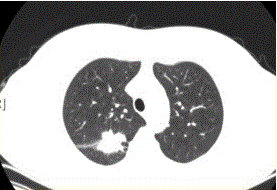

问题 患者女,54岁,无症状,常规体检透视时发现右上肺阴影。既往无结核病史。体格检查阴性。CT结果如下图。 该例最可能诊断为

选项 A.肺结核瘢痕 B.周围型肺癌 C.肺错构瘤 D.肺腺瘤 E.结核球 F.尘肺(硅沉着病)

答案 B

解析 B